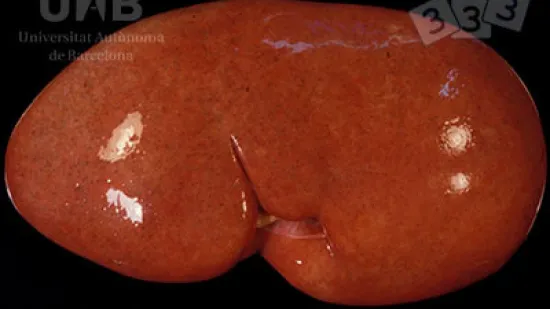

Semaine du 17-Mai-2021

Laquelle de ces bactéries peut produire cette lésion chez les porcelets allaitants ?